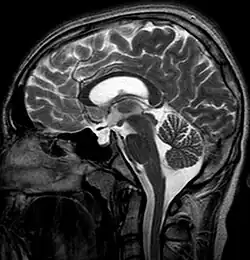

Empty sella in MR imaging

The empty sella sign is a radiological finding characterized by the partial or complete filling of the sella turcica with cerebrospinal fluid (CSF), causing the pituitary gland to appear flattened or compressed against the walls of the sella.[1] This results in the sella appearing "empty" on imaging, despite the presence of a compressed pituitary gland. The empty sella sign is typically identified on magnetic resonance imaging (MRI) or computed tomography (CT) and can be associated with various clinical conditions or incidental findings.[2]

MRI is the gold standard for diagnosing the empty sella sign. Key features include:[5]

• CSF signal: The sella turcica is filled with material that follows the signal characteristics of CSF on T1-weighted and T2-weighted images.

• Flattened pituitary gland: The pituitary gland appears thin and plastered against the sellar floor or walls.

• Enlarged sella: The sella turcica may appear expanded or normal in size.